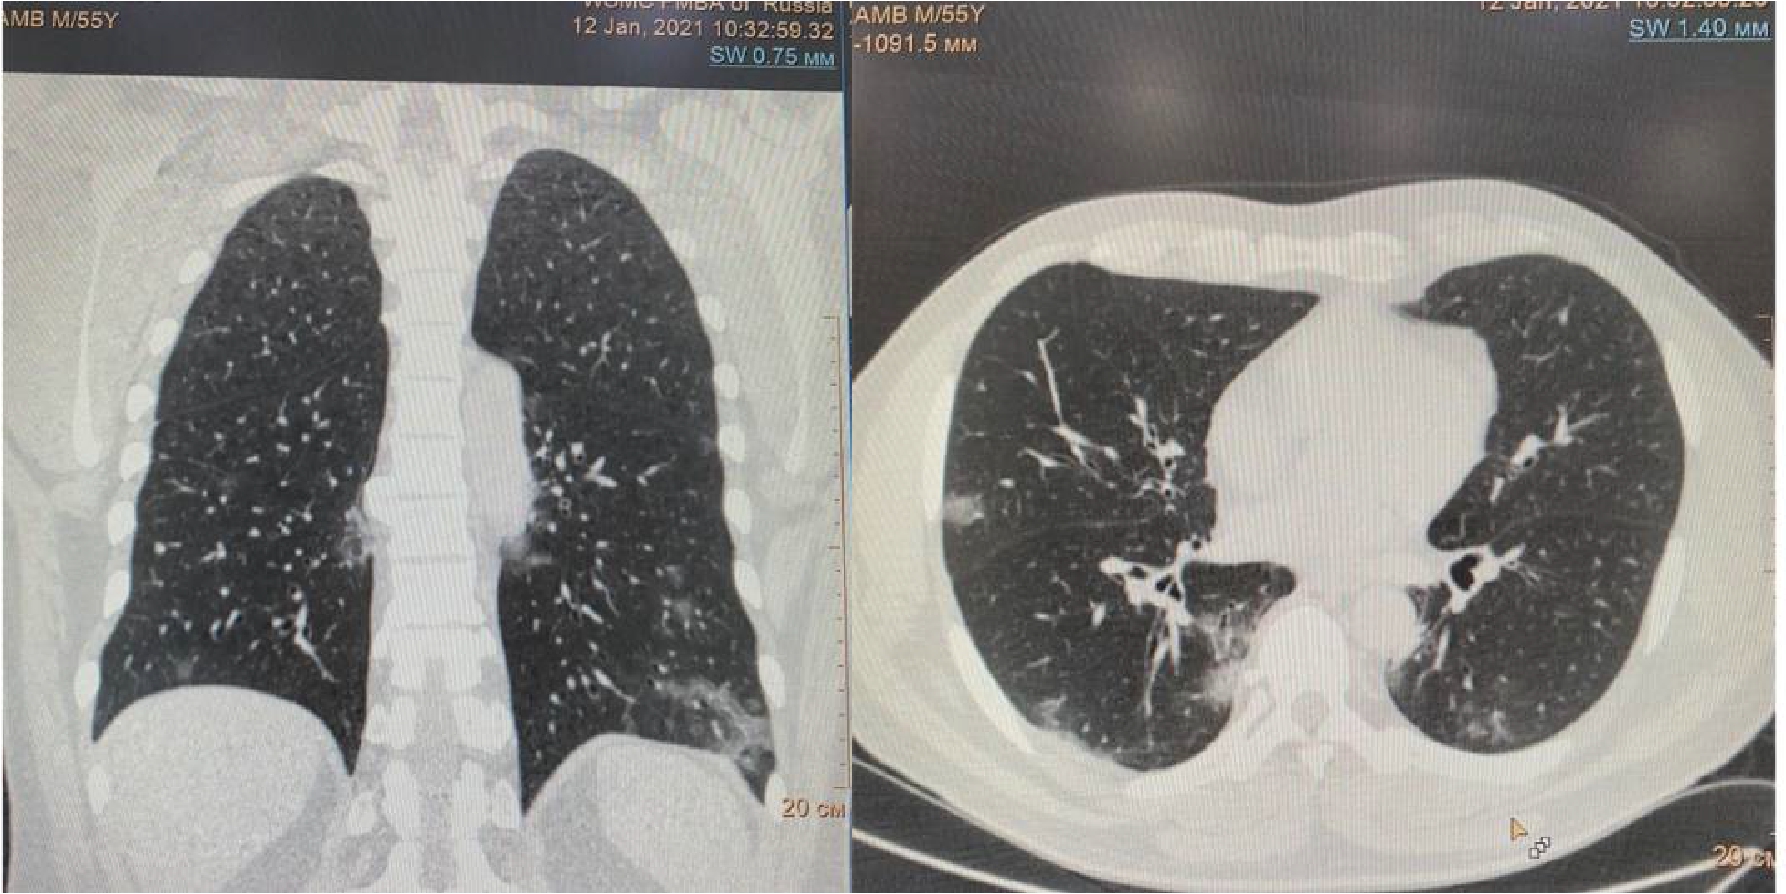

Рисунок 2. МСКТ органов грудной клетки – признаки двусторонней полисегментарной интерстициальной пневмонии (объем поражения 40%, КТ-2)

На 4-е сутки госпитализации выявлено ухудшение клинического статуса (снижение SpO2 до 93%, температура тела более 38 0С), отрицательная динамика по МСКТ (объем поражения 28%, КТ-2, в связи с чем к лечению добавлен олокизумаб однократно, без отчетливого клинического эффекта. На 7-е сутки госпитализации МСКТ выявила дальнейшее прогрессирование поражения легких (объем поражения 40%, КТ-2 (рис.2) на фоне сохранения умеренно выраженного кашля (со скудной мокротой), нарастания дыхательной недостаточности (SpO2 85-88% без инсуффляции кислорода). Больной переведен в отделение анестезиологии и реанимации, где находился в течение 3 суток, лечение включало преднизолон 480 мг/сут (начальная доза), противокашлевый препарат центрального действия (бутамират), проведен плазмоферез (аппарат Fenwal; инфузия плазмы - 2440 мл, эксфузия плазмы - 1430 мл) с введением антиковидной плазмы (270 мл).